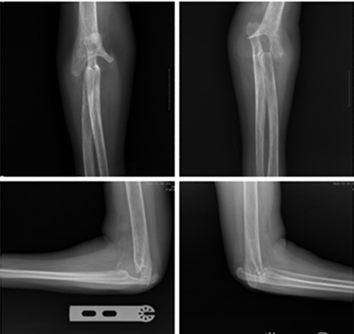

患者王女士,48歲,25年前診斷為類風(fēng)濕關(guān)節(jié)炎。3年前病情突然加重,膝關(guān)節(jié)和肘關(guān)節(jié)完全不能活動(dòng),生活幾乎不能自理。

經(jīng)人介紹,王女士找到了省級(jí)知名骨科專家、邦爾骨科集團(tuán)首席專家、嘉興邦爾骨科醫(yī)院院長(zhǎng)趙凱教授。趙凱教授為王女士會(huì)診后,決定應(yīng)用3D打印技術(shù)為患者定制專屬的肘關(guān)節(jié)假體,進(jìn)行“雙側(cè)人工肘關(guān)節(jié)置換術(shù)”。

患者術(shù)后功能恢復(fù)良好,相比于普通的肘關(guān)節(jié)置換手術(shù),3D打印技術(shù)能夠縮短手術(shù)時(shí)間,手術(shù)更加精確。

術(shù)前顯示:肘關(guān)節(jié)破壞十分嚴(yán)重

(采用常規(guī)的肘關(guān)節(jié)假體,

很難實(shí)現(xiàn)與骨骼的完全匹配)

患者術(shù)后雙肘關(guān)節(jié)的正側(cè)位片